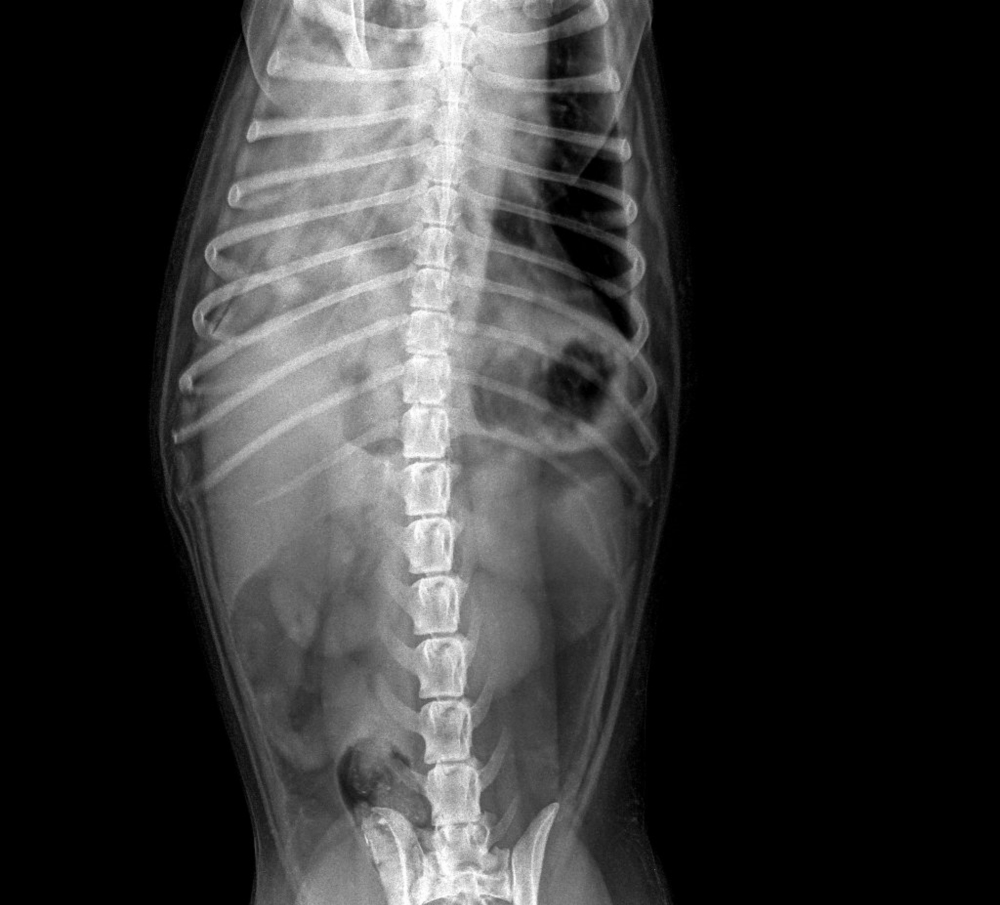

En septiembre de 2016 recae de nuevo con dolor importante en el costado derecho. Es diagnosticada de pneumotórax espontáneo recidivante, objetivándose en la radiografía de tórax y por TAC, el neumotórax extenso derecho, pero sin observarse ninguna otra patología.

Mediante abordaje videotoracoscópico media derecha, se desbridaron bridas pleurales dispersas hasta que se observó una pequeña hernia diafragmática que se reparó con puntos sueltos de monofilamento, sin evidenciarse otras lesiones que pudieran justificar otro origen del neumotórax recidivante. Se procedió posteriormente a la aplicación en la zona pleural de tratamiento químico con talco y cierre dérmico con drenaje, estando la paciente en UCI durante 48 horas para control, y pasando a planta cuatro días más, hasta su alta sin complicaciones.